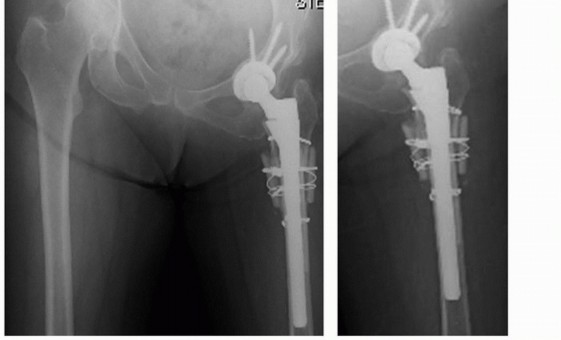

الرحلة الجراحية مع د. محمد هطيف التحضير والتعافي

تعتبر عملية إعادة بناء مفصل الورك المعقدة باستخدام ترقيع رأس الفخذ الذاتي رحلة تتطلب تخطيطًا دقيقًا، مهارة جراحية عالية، ورعاية شاملة بعد الجراحة. يقود الأستاذ الدكتور محمد هطيف هذه الرحلة بخبرته التي تزيد عن 20 عامًا، وهو أستاذ في جامعة صنعاء، ومشهور بتطبيقه لأحدث التقنيات الجراحية مثل جراحة المفاصل الصناعية والمناظير 4K والجراحة المجهرية.

الإجراء الجراحي (الخطوات التفصيلية)

تُجرى الجراحة تحت التخدير العام وتستغرق عادةً عدة ساعات نظرًا لتعقيدها. يستخدم الدكتور هطيف أساليب جراحية دقيقة لتقليل فقدان الدم وتسريع التعافي.

مزايا ترقيع رأس الفخذ الذاتي

- التوافق الحيوي الأمثل: نظرًا لأنه عظم المريض نفسه، فإن خطر الرفض أو التفاعلات المناعية معدوم.

- الاندماج العظمي (Osteointegration): يندمج الطعم العظمي بشكل طبيعي مع عظم الحوض المحيط، مما يوفر دعمًا بيولوجيًا قويًا ودائمًا.

- قوة ميكانيكية: يوفر دعمًا هيكليًا ممتازًا يمكن أن يتحمل الأحمال الطبيعية.

- تصحيح تفاوت طول الساقين: يساهم في تحقيق طول ساقين متساوٍ، وهو أمر بالغ الأهمية لوظيفة المشي والوقاية من مشاكل الظهر.